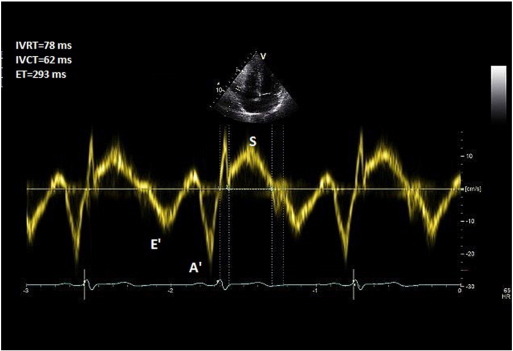

TDI is deployed at the lateral tricuspid annulus with a sweep speed of 100 mm/s. Pulse wave (PW) Doppler with a 6 mm sample window is obtained. Right ventricular isovolemic relaxation time (r IVRT) is measured from the offset of the S′ wave to the onset of the E’ wave (Fig. 7 ). r IVRT of > 75 ms reliably predicts pulmonary hypertension while an r IVRT of < 40 ms has a high negative predictive value for pulmonary hypertension [25] and [26] .

|

Fig. 7. Right ventricular isovolemic relaxation time measurement. |

Coaxial tricuspid TDI is may not be possible in all patients and incident angle should be no more than 15°. The technique may become unreliable in hypertrophic cardiomyopathy, right bundle branch block and right ventricular dysfunction because the r IVRT is prolonged for other reasons. On the other hand, r IVRT is pseudo-normalised in the presence of elevated RAP and significant TR [27] .